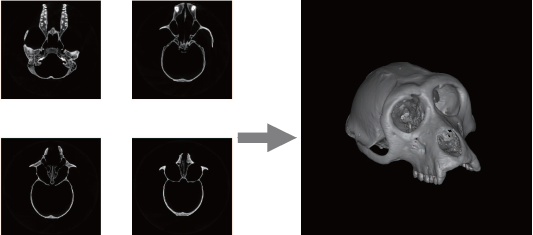

图1 基于颅骨CT扫描和线性插值的三维颅骨模型重构